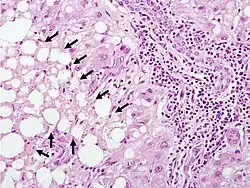

The second phase occurs between 24 hours and 72 hours following overdose and consists of signs of increasing liver damage. In general, damage occurs in liver cells as they metabolize the paracetamol. Hallmark pathology on liver biopsy includes regions of coagulative necrosis in zone 3 of the liver acinus, around the central venules, as these hepatocytes have higher concentrations of cytochrome P450 enzymes compared to zone 1 hepatocytes surrounding the portal venule of the acinus. Remaining viable hepatocyes frequently show ballooning injury and steatosis. [13] The individual may experience right upper quadrant abdominal pain. The increasing liver damage also changes biochemical markers of liver function; International normalized ratio (INR) and the liver transaminases ALT and AST rise to abnormal levels.[14] Acute kidney failure may also occur during this phase, typically caused by either hepatorenal syndrome or multiple organ dysfunction syndrome. In some cases, acute kidney failure may be the primary clinical manifestation of toxicity. In these cases, it has been suggested that the toxic metabolite is produced more in the kidneys than in the liver.[15]